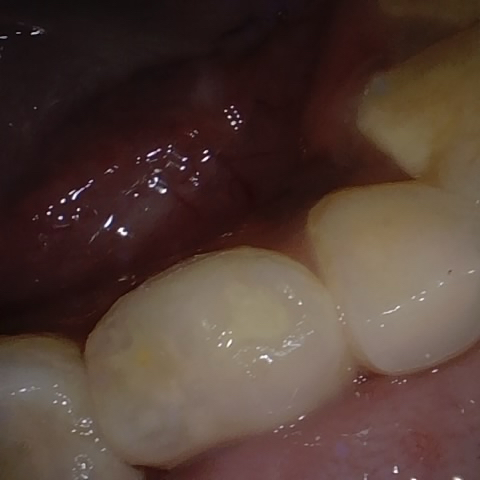

Annotated as "Good"